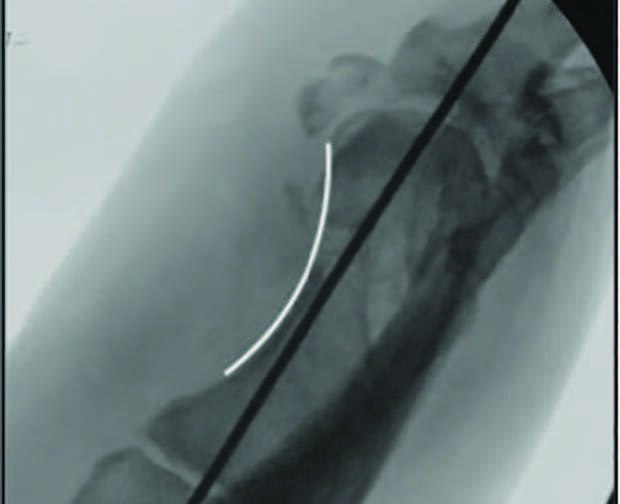

Due to the displacement of the capital fragment and the potential for osteomyelitis, we performed a hardware removal and stabilized the first metatarsal head with a 0.062-inch K-wire. The dorsal cortex was comminuted, which led us to pack bone chip allograft and bone marrow aspirate the dorsal wing of the osteotomy.7,8 We instilled vancomycin powder at the bone/capsule interface and closed the capsule.9,10 The first metatarsal head and proximal phalanx stabilization then took place with a mini external fixator.11-14 The recurring surgical incision site was left open, and negative pressure wound therapy allowed secondary closure.

Intraoperative bone biopsy and cultures of deep tissue and bone did not reveal infection. We kept the patient non-weight-bearing for eight weeks, at which time we removed the external fixator. Consolidation and healing of osteotomies developed over serial radiographs. The patient then began using a CAM boot, and weight-bearing ensued in this fashion for a further four weeks. Complete healing of both osteotomies occurred at 12 weeks postop. The patient received a new accommodative foot orthotic, and no recurrent ulceration has occurred.